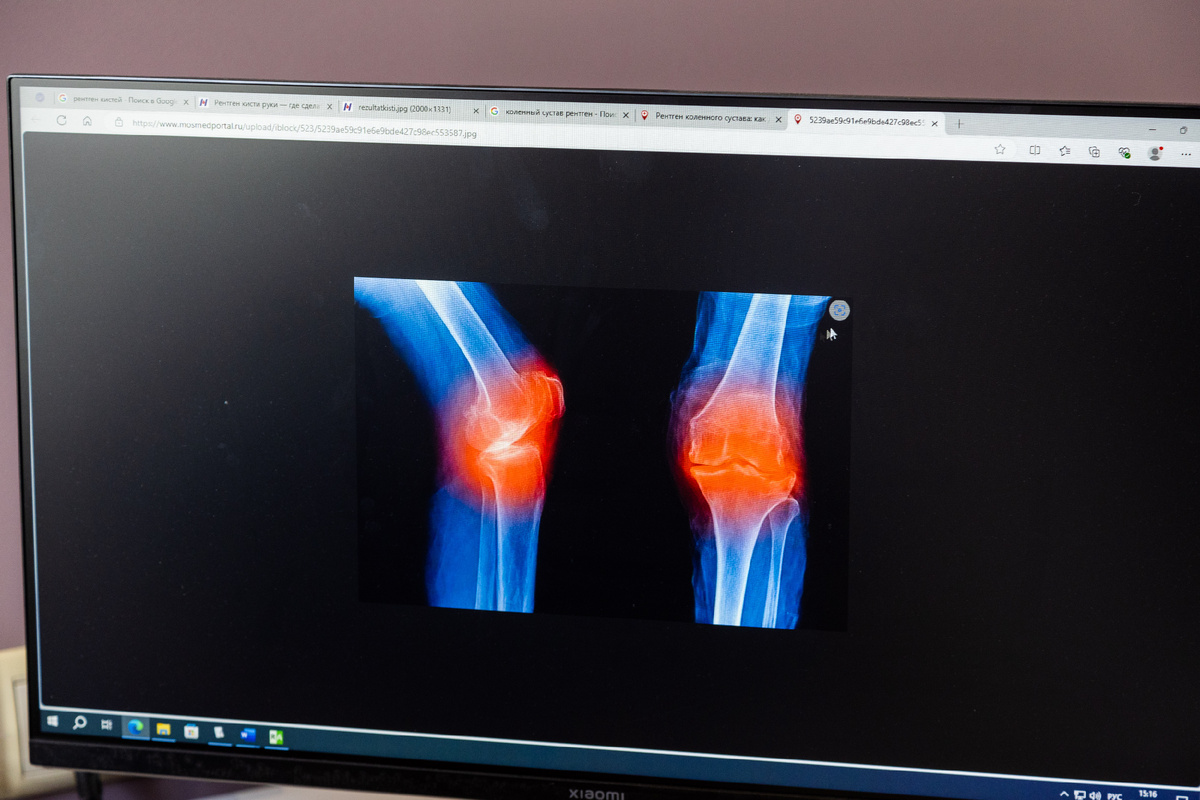

Боли и припухлости в коленях, невозможность ходить, слабость в ногах – всё это потенциальные признаки кисты Бейкера.

Для остальных поясню – это новообразование, которое возникает вследствие вытекания синовиальной жидкости из полости сустава в сумку на задней поверхности. Если совсем по-простому, грыжа в области колена.

В диагностике коленного сустава ОЧЕНЬ важную роль играет ультразвуковое исследование. УЗИ позволяет быстро определить, к кому направлять пациента – ревматологу, травматологу или к сосудистому хирургу с лимфостазом. Дальше – точнее сориентироваться с патологией.